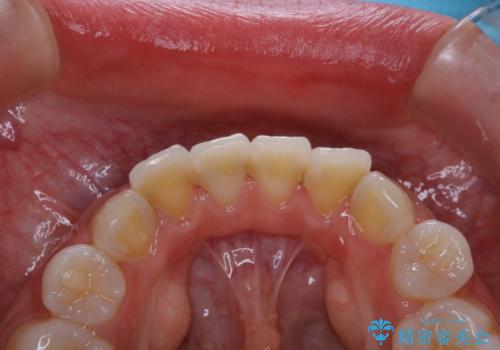

- これから矯正治療を始めるため、今の状態でも歯をきれいにしておきたいとのことでした。PMTC60分コースを行いました。

プラーク(細菌の塊)や歯石がたまると歯の表面はザラつきいてきます。そのザラつきは歯周病や虫歯菌の棲家となります。そのまま放置すると、歯肉が腫れてきたり、歯肉から出血したり、口臭が強くでたりします。とくに歯肉の境目は、歯磨きで汚れを除去することが難しく、プラーク(細菌の塊)や歯石が溜まりやすい場所です。

歯並が、がたついている場合はなおさら汚れが溜まりやすいです。矯正治療前や矯正中、定期的にPMTCをすることで、矯正治療中の歯肉トラブルを防ぐことにつながります。